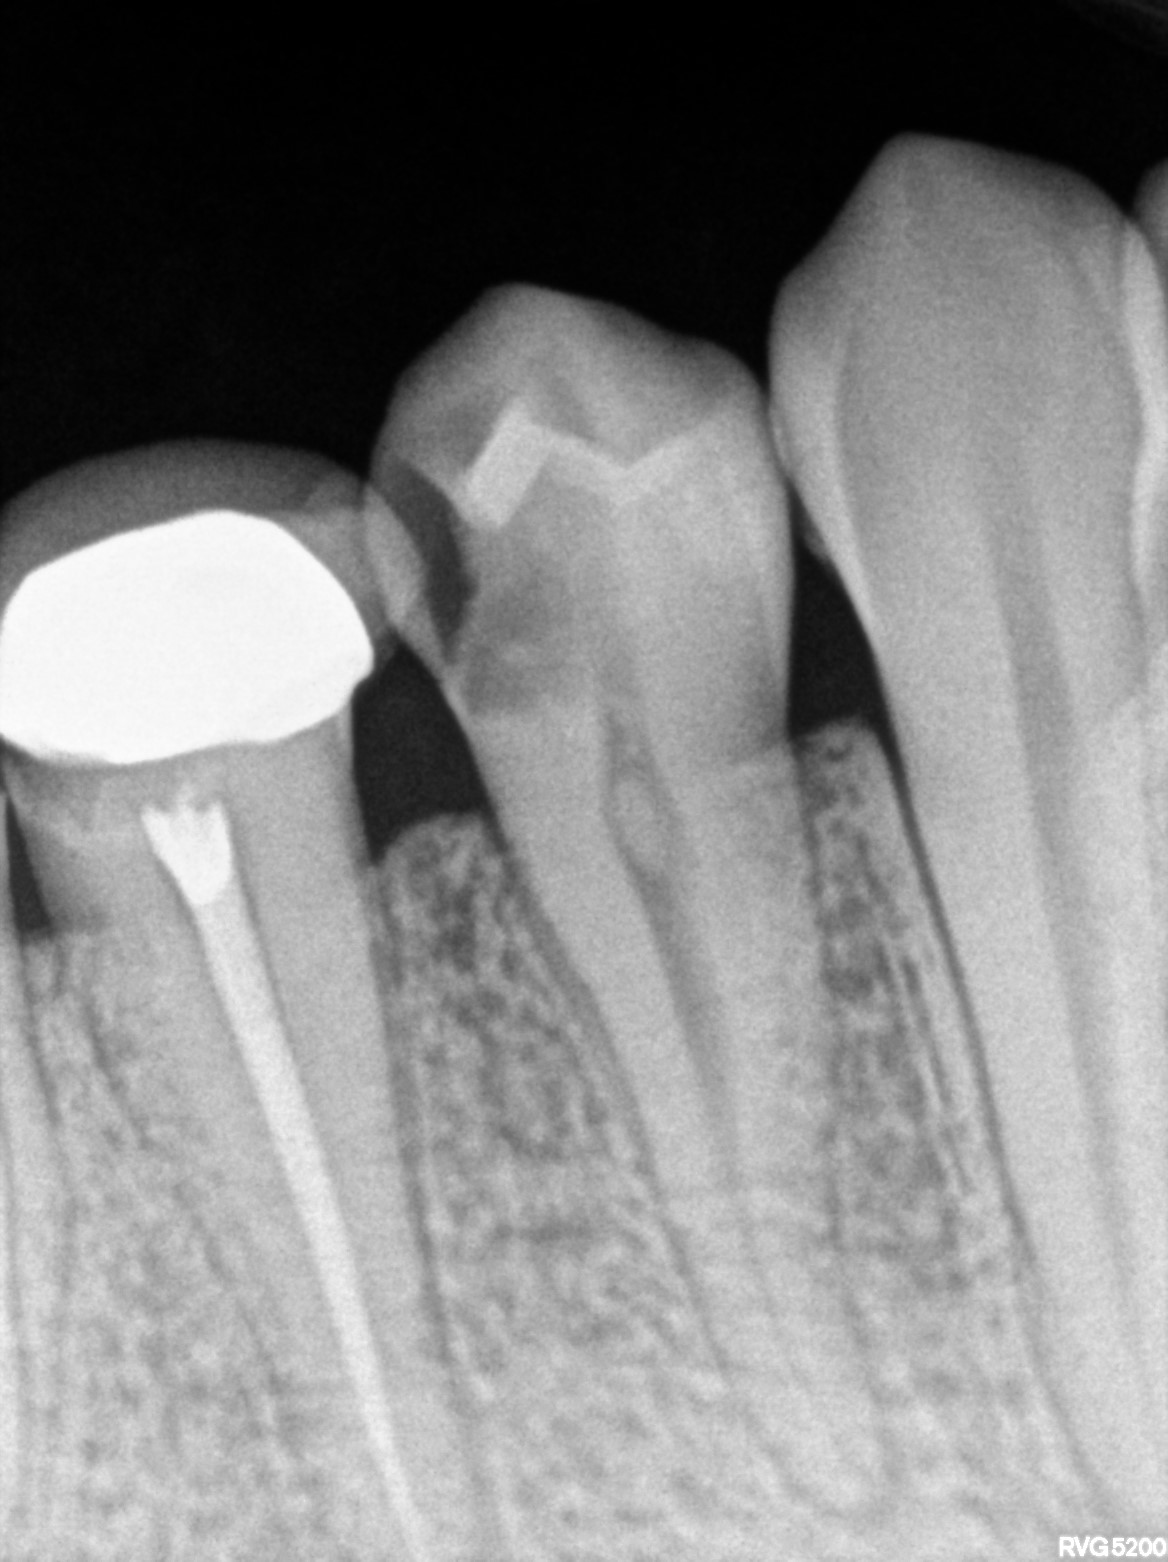

Dental Radiographs FHIR: DocumentReference · LOINC 24641-7

R59.jpg

24641-7

| Root canal treatment | 234780006 | D3310 Endodontic therapy, anterior tooth | ##43, #44 | 2026-02-05 | completed | adv rct with 43 44 | |

| 2026-02-05 21:53 | fulfilled | adv rct with 43 44 | |